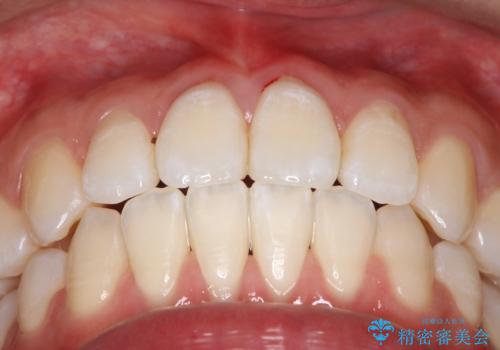

【ワイヤー矯正】前歯の突出感、下の歯の並びを良くしたい

- 主訴:上の前歯の突出感と下の歯の並びを改善したい

非抜歯にて矯正治療を行いました。

IPRを行い、前歯部の突出感の改善に努めました。

期間:1年9カ月